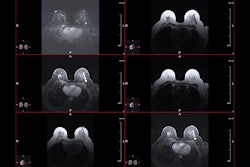

The training set included 90 women, while the external test set included 29 women. Two radiologists evaluated MRI features, including percentage enhancement reduction, which assessed relative expansion of intralesional non-enhancing components after early neoadjuvant chemotherapy.

MR image from a 55-year-old patient with triple-negative breast cancer from training set. (A, above) Axial postcontrast T1-weighted image from baseline MRI exam shows unifocal enhancing mass (unifocality: positive). (B, below) Axial postcontrast T1-weighted image from MRI examination per-formed after one cycle of neoadjuvant chemoimmunotherapy shows >37% reduction in lesion size (early tumor shrinkage: positive) and development of non-enhancing region within lesion (percentage enhancement reduction: positive).ARRS

In the external test set, the resulting model achieved an area under the curve (AUC) of 0.88, 74% sensitivity, and 90% specificity for predicting complete pathologic response. The Hosmer-Lemeshow test showed satisfactory model fit (p = 0.67). The team also reported substantial interobserver agreement for focality (Cohen's kappa coefficient [κ] = 0.7), early tumor shrinkage (κ = 0.66), and percentage enhancement reduction (κ = 0.61).